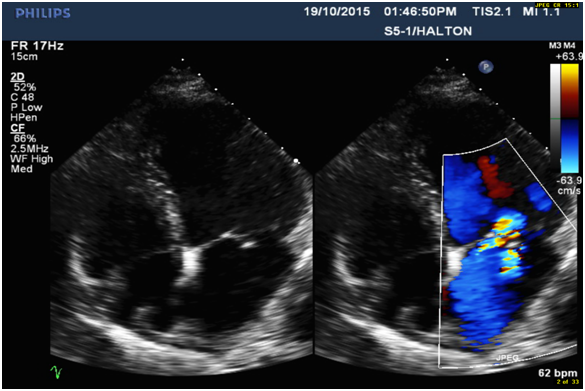

5. Eccentric anteriorly directed severe MR jet area over 50% (Figure 2) with MR ERO 0.47cm2 (Figure 3) and Vena Contracta 0.76cm (Figure 4), which is consistent with posterior flail leaflet of MVP.

Figure 4: Anteriorly directed eccentric MR jet (TEE) due to P2 segment defect of flail posterior leaflet with the vena contracta (0.76cm), consistent with severe regurgitation.

Diagnosis of MVP with flail posterior leaflet and grading of MR severity

Physical examination and 2-dimensional (2D) echocardiography are the diagnostic gold standards for MVP [4]. According to echo findings I listed above, together with the patient’s symptoms (SOB and chest discomfort) and pansystolic murmur heard at the apex, the patient was diagnosed as severe MVP with flail posterior leaflet. Echo criteria of flail leaflet includes leaflet tip pointing to LA without systolic coaptation (Figure 1,2,4), torn chordae, double contour (parallel sign) between flail and normal leaflets (Figure 4), and eccentric MR jet direction opposite to the location of the flail leaflet (Figure 2 and 4) [3,4]. Doppler echocardiography is essential in determining the severity of MR. According to ASE guideline, criteria for severe MR includes a vena contracta width ≥ 0.7 cm, large central mitral regurgitation jet (area >40% of left atrium), pulmonary vein reversal, effective regurgitant orifice >40 mm2 and others [3,5]. The echo findings and Doppler measurements strongly support a severe MR in the patient (Table 1).

Differential diagnosis

When MVP with flail leaflet was diagnosed by TTE, next step should consider which scallop segment can be involved in the defect. TEE is effective in identifying prolapsing segments with multiple plans. Anatomically, the posterior and anterior leaflets of the mitral valve each may be divided into three sections. Carpentier’s widely recognized nomenclature describes three posterior leaflet scallops–the lateral (P1), middle (P2), and medial (P3)-and three anterior segments (A1), (A2) and (A3) [2,3]. According to clinical studies, P2 is the most common site of localized prolapse and flail due to myxomatous degeneration and fibroelastic dysplasia [2]. In this study, localized P2 segment defect was identified by sagittal view (long axis) of TEE.